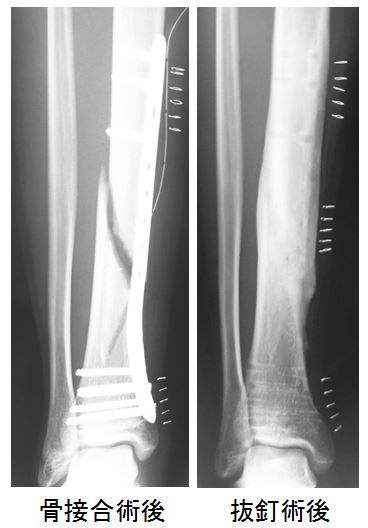

先日、脛骨遠位部骨折に対する抜釘術を施行しました。

初回手術は骨端が閉鎖していなかったため、髄内釘ではなくロッキングプレートを選択しました。

脛骨遠位1/3での骨折であったため、可能なかぎり軟部組織への侵襲を少なくする必要があります。そこで、骨折部は展開せずにMIPOの手技で骨接合を行いました。

今回の症例でも脛骨遠位1/3での第3骨片を伴う分節型骨折でしたが、特に問題なく骨癒合を獲得することができました。

しかし、抜釘術の段階で少しつまずきました。ある程度予想はしていましたが、骨折部でプレート周囲表面が新生骨に覆われてしまったため、追加で新しい皮膚切開が必要になったのです。